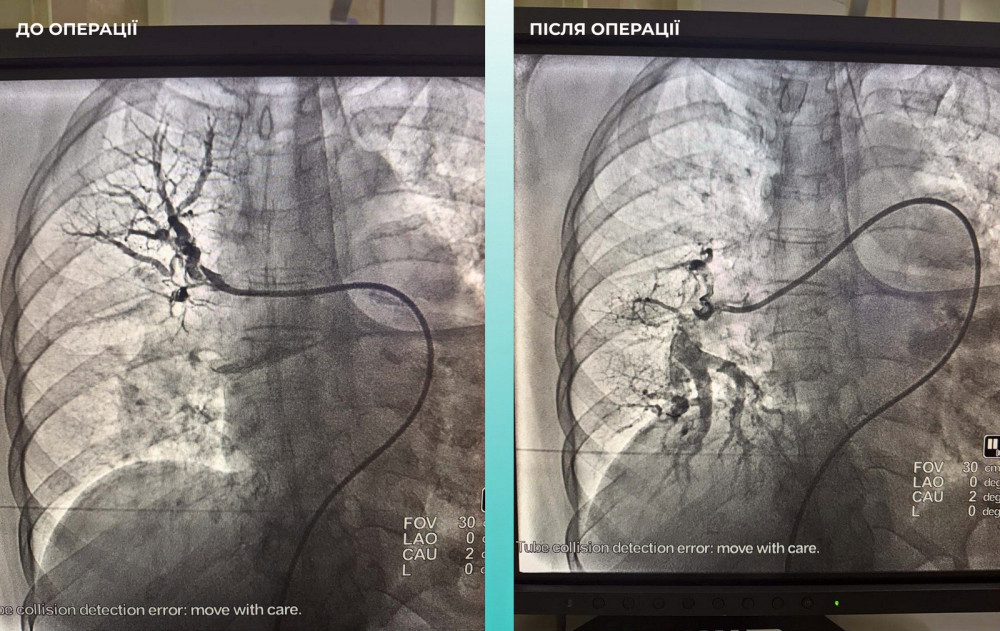

Команда лікарів ухвалила складне, але вкрай необхідне рішення — провести одночасну тромбектомію обох артерій.

Операція пройшла успішно, і зараз пацієнтка почувається значно краще: вона в свідомості та вже може рухати кінцівками.